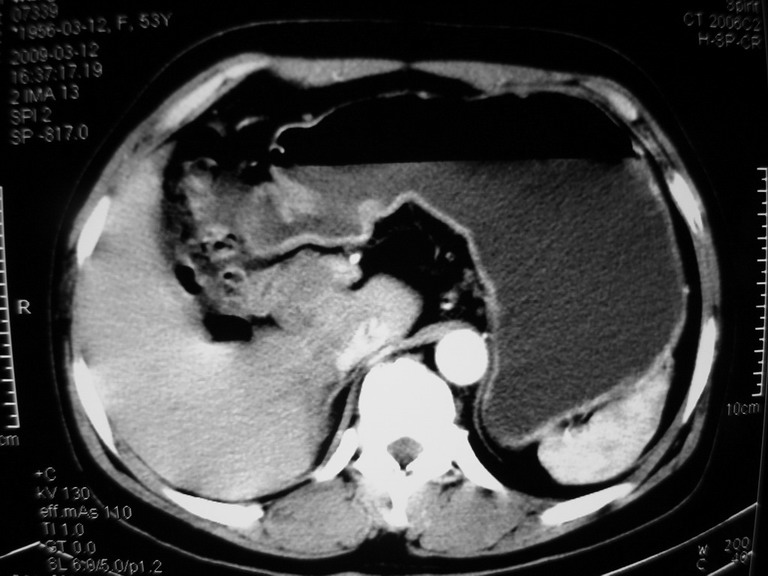

患者,女性50岁,上腹部不适2年余,既往多次腹部彩超未见异常,今日上午在我院查彩超发现肝右叶囊实性病变,外院辅助检查,afp,cea,ca199, 都在正常范围内,无肝炎史否认肿瘤史,生活在牧区

接着往下一贴看,有静脉期和延迟期,在看看和下腔静脉及十二指肠的关系,腔静脉内是不是栓子?

考虑肝右叶与尾叶交界区肝癌(部分外生),侵犯下腔静脉并下腔静脉瘤栓形成。